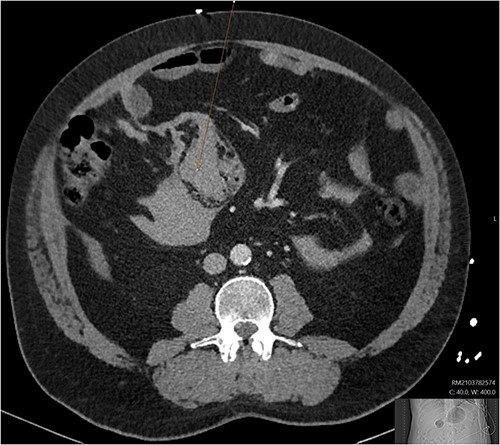

A CT abdomen-pelvis (CT-AP) revealed an acute haematoma inferolateral to the third part of the duodenum and another at the root of the mesentery. High density fluid related to the mesenteric bleed was also seen extending from the right para-colic gutter into the pelvis and in the peri-hepatic region. The patient was admitted under general surgery, stabilized with intra-venous fluid resuscitation, co-amoxiclav and metronidazole and cross matched for four units of blood. A CT-angiogram demonstrated acute haemorrhage throughout the abdomen with a 104 x 62 mm haematoma arising centrally at the level of L2 within the mesenteric fat (Fig. 1). The haematoma did not appear to originate from any specific mesenteric vessels but was related to some mid and distal jejunal loops. The angiogram also showed discontinuity when tracing the proximal and mid jejunal loops inferiorly, extensive haemorrhagic peritoneal fluid around the liver extending inferiorly (Fig. 2) and a small amount of peri-splenic haemorrhagic fluid. Curved reformatting of the angiogram revealed no abnormalities within the superior mesenteric artery (Fig. 3).

CT angiogram showing a large acute mesenteric haematoma. Figure 1 is taken from an axial section of the patient’s initial CT angiogram of the abdomen and pelvis. The arrow shown highlights an area of high-density fluid representing a 104 x 62 mm acute mesenteric haematoma.